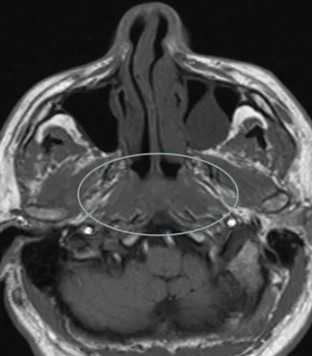

Не возникало сложностей в выявлении опухолевых узлов Т3, Т4 стадий, имевших все отмеченные выше признаки в различных сочетаниях в 36 исследованиях (рис. 11). Из 50 обследованных с помощью МСКТ и МРТ пациентов у 26 (52,0%) были выявлены метастазы в лимфатических узлах шеи. Поражались преимущественно лимфатические узлы I-II уровня. Признаками метастаза плоскоклеточного рака в лимфатических узлах были: увеличение размера лимфатического узла более 1,0 см, изменение формы лимфатического узла с бобовидной на округлую, структурные нарушения в узле, нечеткость наружных контуров узла, уплотнение окружающей жировой ткани на КТ или изменение сигнала на МРТ.

Большинство пораженных метастазами лимфатических узлов имели размеры более 1,0 см, округлую форму (рис. 12). Внутривенное контрастирование при оценке изменений в лимфатическом узле являлось обязательным условием для уточнения внутренней структуры и выявления зон некроза. В результате гипоксии и распада ткани формируется центральная зона некроза, не накапливающая контрастный препарат при внутривенном болюсном усилении. При этом отмечается повышение плотности в периферических отделах лимфатического узла (рис. 13).